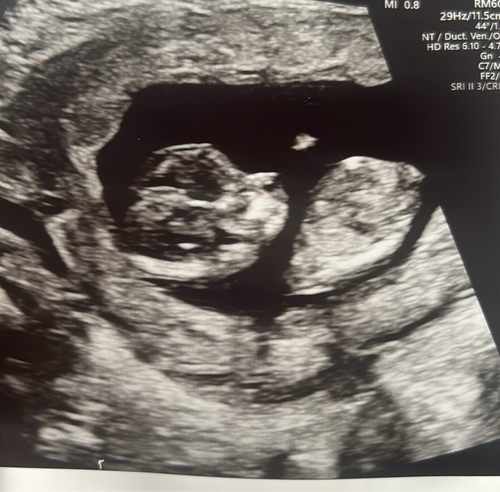

Endlich ein Herzschlag & 2 stolze CM groß bei 8+4

Das war 6+5 man konnte den Herzschlag schon sehen 🥹😍und hoffe nächste Woche kommt das nächste

Unser Wunder bei 7+1 ❤️

7+5ssw🙃